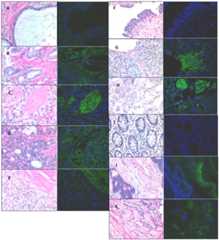

OATP protein expression versus tumor differentiation

To determine if OATP translation is similar to the quantitiative PCR, we conducted immunoflourescence on tissue samples from prostate, colon, and bladder cancer to detect OATP1B3. OATP2B1 was not chosen for protein validation because it is expressed both in normal and cancerous tissues. For prostate tumors, expression of OATP1B3 was primarily observed in prostate tumors and not normal tissues (P = 0.001;Figure 3A–E andTable 1) and was highly expressed in the stroma. Moreover, the frequency of OATP1B3 expression varied significantly with Gleason score (P = 0.001;Table 1). Expression was also more frequent in colon cancer (P = 0.06,Figure 3F–H andTable 1) and trended towards an association with a statistically significant higher incidence of expression in colon cancer by Cochran-Armitage test (P = 0.02;Table 1). OATP1B3 expression was observed primarily in the vasculature in colon cancer and invasive, cancerous epithelial cells in bladder cancer. Consistent with the mRNA data, OATP1B3 expression was not associated with increasing histological grades of bladder cancer (P = 0.34; seeTable 1 andFigure 3I–K), but trended towards an association with bladder cancer grades despite a low number of samples (P = 0.07; seeTable 1).

Figure 3. Tissue staining of OATP1B3 expression in cancer.

Concurrent tissue sections stained with hematoxylin and eosin (left panel) and immunofluoresence (right panel) for OATP1B3. OATP1B3 is detected with FITC, in green, and nuclei are stained with DAPI, in blue. Prostate tissues comprising, BPH, and tumors of varying grade are reported as follows: A) benign prostatic hyperplasia, B) gleason 6, C) gleason 7, D) gleason 8, E) gleason 9. Bladder tissue sections are derived from F) normal bladder, G) grade II, H) grade III bladder tumors. Finally, colon tissue from I) normal colon, J) grade II (10x magnification), K) grade III colon tumors are disclosed. All photos were taken at 40x magnification unless otherwise noted.